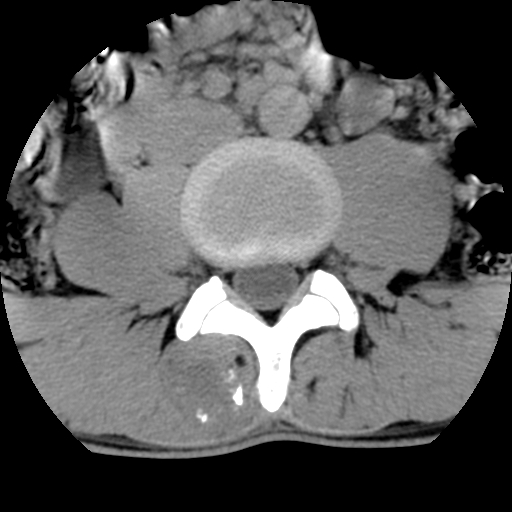

男,腰背痛

本人诊断1tb2包虫,请会诊

1)右侧竖脊肌稍低密度肿块伴钙化(性质待定),不排除肿瘤可能;建议行进一步检查。2)腰椎间盘突出。

1.右侧竖脊肌软组织肿块伴团块状钙化,首先考虑血管瘤可能性大;建议行进一步检查;2。腰椎间盘突出。